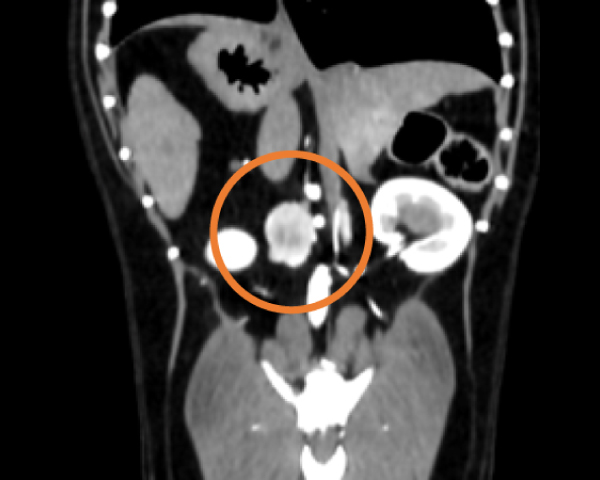

造影CT検査にて腫瘤の浸潤を評価

腹腔鏡を用いた副腎腫瘍摘出術